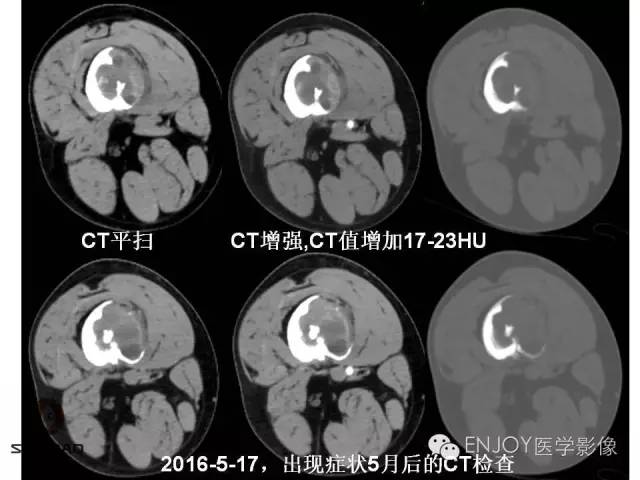

【病例】右侧股骨多形性肉瘤1例X线及MR影像表现

多形性肉瘤(以往称为:恶性纤维组织细胞瘤)